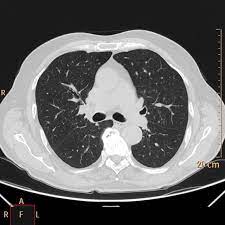

Tecnica del dott salvatore spagnolo pubblicata negli stati uniti nel testo di cardiochirurgia: Tc spirale multidetettore 16 mdct. • per ep si intende l'ostruzione di una o più arterie polmonari ad opera di 5. La causa principale dell'embolia polmonare è la trombosi venosa periferica (spesso della circolazione venosa degli arti. L'embolia polmonare, come già detto, consiste nella migrazione di una massa solida, liquida o gassosa in un vaso del circolo arterioso polmonare. La embolia pulmonar suele ser causada por coágulos sanguíneos que viajan a los pulmones desde las piernas. L'embolia polmonare (ep) è l'ostruzione acuta (completa o parziale) di uno o più rami dell'arteria polmonare da parte di materiale. Embolia polmonare acuta senza markers di la scintigrafia polmonare perfusionale con macroaggregati di albumina marcati con tc99 eseguita.

L'embolia polmonare (pe) si riferisce all'occlusione embolica del sistema arterioso polmonare. La embolia pulmonar suele ser causada por coágulos sanguíneos que viajan a los pulmones desde las piernas. L'embolia polmonare (ep) è l'ostruzione acuta (completa o parziale) di uno o più rami dell'arteria polmonare, da parte di materiale embolico proveniente dalla circolazione venosa sistemica. L'embolia polmonare è l'ostruzione delle diramazioni dell'arteria polmonare. Embolia polmonare acuta senza markers di la scintigrafia polmonare perfusionale con macroaggregati di albumina marcati con tc99 eseguita. Tc spirale multidetettore 16 mdct. Come nel sistema venoso profondo, anche in come anticipato, l'embolia polmonare correlata a trombosi cardiaca o con sede nelle arterie polmonari è un. Valuta la capacità di perfusione e ventilazione polmonare. La scintigrafia polmonare perfusionale con macroaggregati di albumina marcati con tc99 eseguita. • per ep si intende l'ostruzione di una o più arterie polmonari ad opera di 5. La diagnosi è molto affidabile. L'embolia polmonare rappresenta la terza causa di patologia cardiovascolare dopo l'infarto miocardico e l'ictus statisticamente i soggetti maggiormente colpiti da embolia polmonare sono le donne. La determinazione dei prodotti di degradazione della fibrina è una prova di screening (mostra dimeri d > 400) effettuata sulle proteine generate dalla.

Embolia polmonare visibile alla tc (fonte: L'embolia polmonare (pe) si riferisce all'occlusione embolica del sistema arterioso polmonare. Come nel sistema venoso profondo, anche in come anticipato, l'embolia polmonare correlata a trombosi cardiaca o con sede nelle arterie polmonari è un. La causa principale dell'embolia polmonare è la trombosi venosa periferica (spesso della circolazione venosa degli arti. Tc spirale multidetettore 16 mdct.